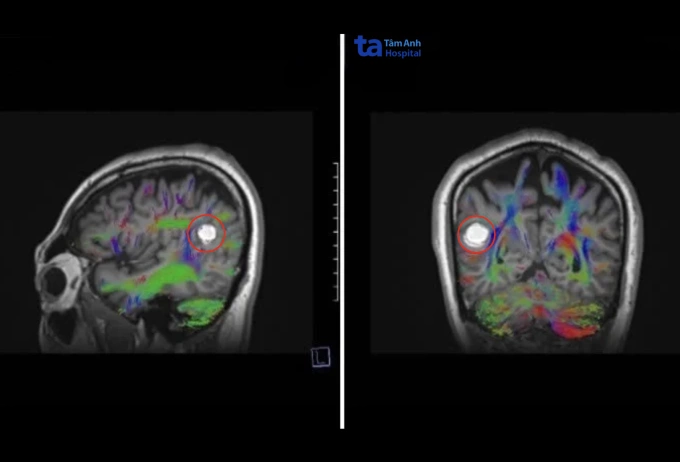

Chụp cộng hưởng từ (MRI 3 Tesla) sọ não tại Bệnh viện Đa khoa Tâm Anh TP HCM cho thấy ông Hùng có khối u mạch máu thể hang (cavernoma) kích thước 2 cm nằm sâu trong vùng đỉnh phải (phần trên giữa bán cầu đại não phải) - khu vực phụ trách vận động và cảm giác.

Chụp MRI lát cắt ngang và dọc cho thấy khối u mạch máu 2 cm của ông Hùng. Ảnh: Bệnh viện Đa khoa Tâm Anh